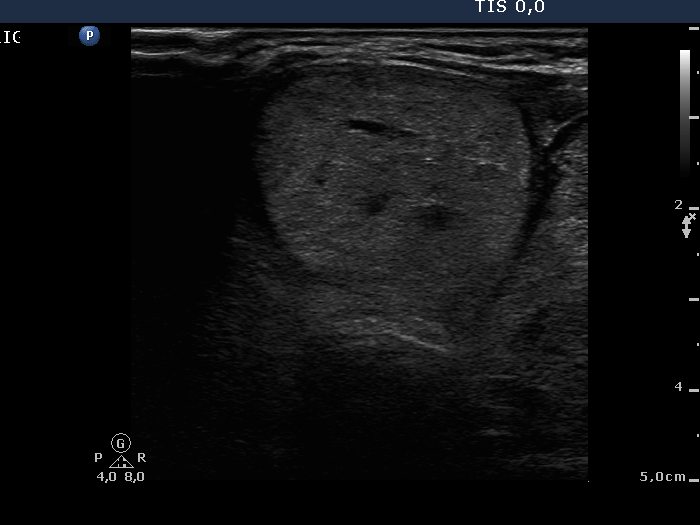

Intact right lobe without any pathological finding and benign hyperplastic nodules in the left lobe (histological diagnosis) - case 803

Right lobe

Left lobe

Both the pseudonodule in the right lobe (upper images) and the benign nodule in the left lobe (lower images) have numerous pale granules and lines which correspond to the normal architecture of the thyroid and correspond to a connective tissue. The finding of a few more bright granules and lines are the ultrasound presentation of a thickened connective tissue.